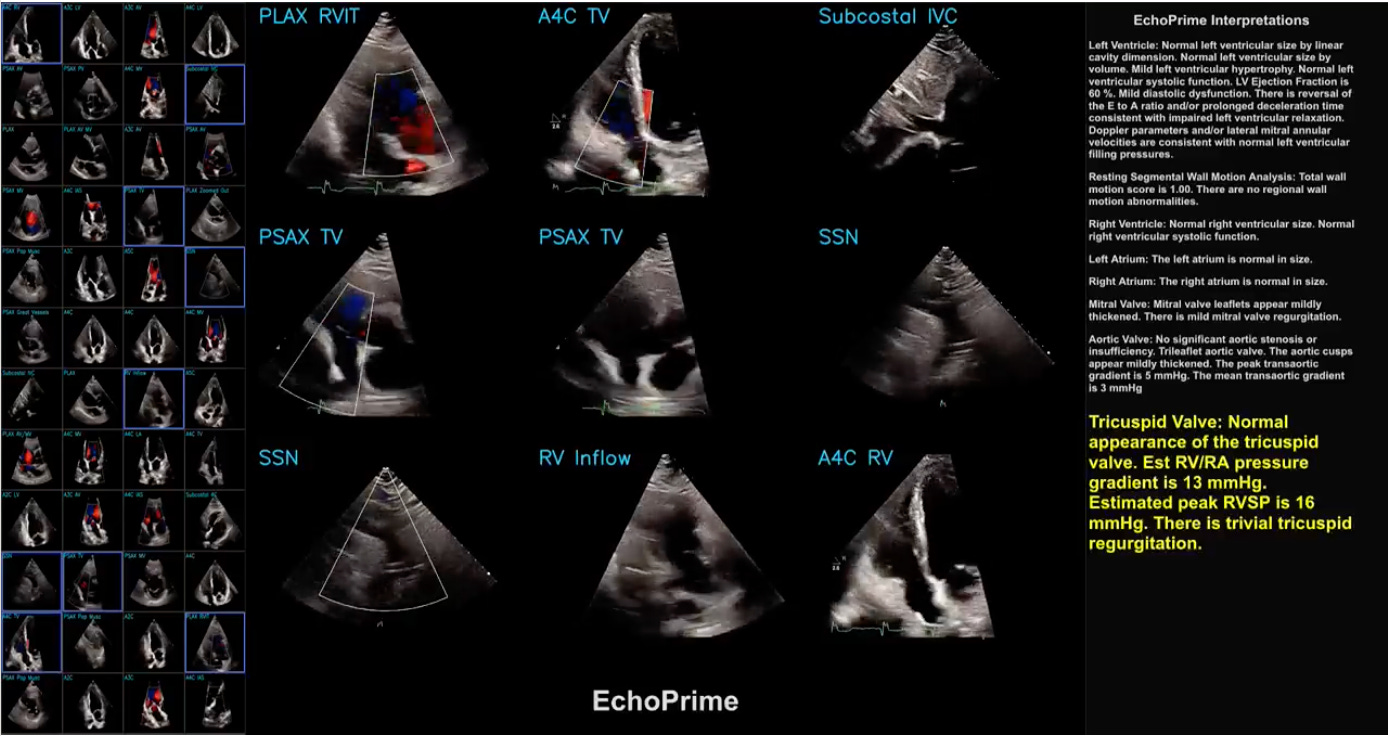

The BrainX Community Live event featured a presentation on AI for comprehensive transthoracic echocardiogram exam interpretation, showcasing the EchoPrime model's capabilities in automating echocardiography analysis and report generation.

EchoPrime, a multi-view, view-informed, video-based vision-language foundation model trained on over 12 million video-report pairs. The presenters discussed the model's technical aspects, training process, and performance, highlighting its potential to improve healthcare outcomes and democratize access to medical expertise.

The model was trained on 2 Nvidia Rtx A 6,000 Gpus with a batch size of 32. The training took approximately one month. The model was trained to analyze echocardiograms and use synthesized information across the whole study. The results showed that as more data was included, the accuracy progressively improved. EchoPrime outperformed previous models on all tasks, particularly those requiring temporal information.

The presenters also compared EchoPrime with task-specific models and found that EchoPrime either outperformed or matched their performance. The event concluded with discussions on the future directions of AI in healthcare, including the integration of more medical modalities and the importance of collaboration between clinicians and engineers in model development and validation.